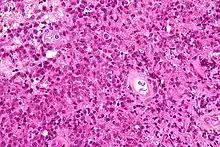

The current standard for diagnosis typically includes positive CSF cytology, vitreous biopsy, or brain/leptomeningeal biopsy.[10] Histopathological confirmation is essential for definitive diagnosis.[11]

Most PCNSLs are diffuse large B cell non-Hodgkin lymphomas.[12][13]